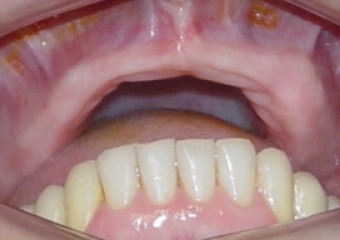

Imagem inicial